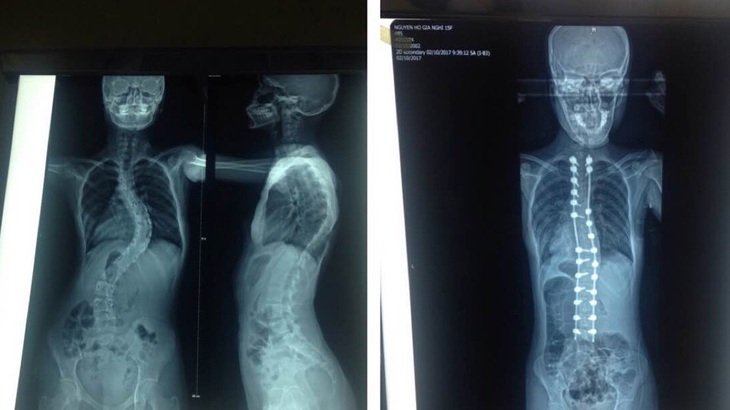

Sản phụ người Campuchia thoát cửa tử ngoạn mục do mắc hội chứng Marfan hiếm gặp - Ảnh: Bệnh viện cung cấp

Bệnh nhân là chị S.K. (36 tuổi, ngụ Campuchia) mang hội chứng Marfan bị lóc tách động mạch chủ cấp tính loại A và phình gốc động mạch chủ (tình trạng tim mạch cực kỳ nguy kịch, đe dọa tính mạng của cả người mẹ và thai nhi).

Các bác sĩ Bệnh viện Chợ Rẫy cho biết hội chứng Marfan là bệnh lý di truyền tương đối phổ biến (tỉ lệ 1/3.000 - 1/5.000), nhưng không phải người bệnh nào cũng gặp biến chứng nặng như phình hoặc lóc tách động mạch chủ khi mang thai.